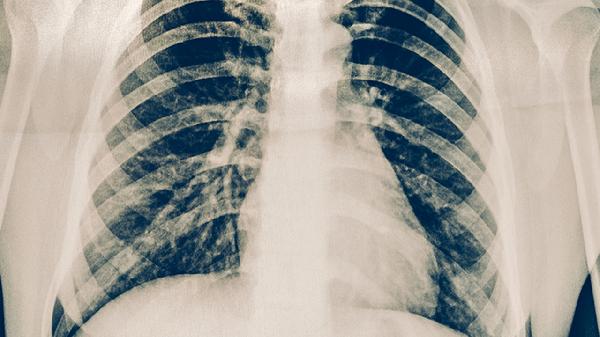

3、针对性肺部检查

根据医生建议选择低剂量CT等检查方式,这类检查辐射量小,能清晰显示肺部细微结构。